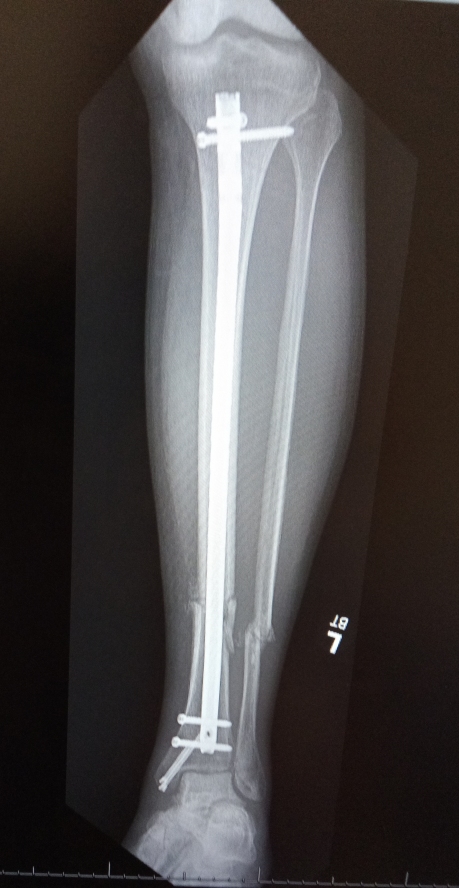

File: leg.jpg (198.4 KB)

>>23722059

I'm still the OG, just a kaizo ningen now

>>23724395

that's one ugly break

>>23724412

yeah I'm mostly healed up but it was rough

>>23724427

motorcycle accident?

>>23724952

close, car blasting out of a stop sign vs me using the crosswalk on my bicycle

I'm mostly better, some lingering nerve damage on my thumb and some aches and pains, but enough to make me realize it could be a whole lot worse

ngl I really do get a kick out of the basic idea that i have metal parts, like that doofy grin the Yakuza guy has when he's low-key bragging to his flunkies about being a Shocker goon, I get that at least twice a day when I think about stuff like "my arm's specs are rated for up to 600lbs" and then I remember that aside in GITS about Batou and why your cyberarm is cool but you need a cybershoulder attached too

I'm pretty "better" by this point, tbdesu I'm really in a better spot than I was before the crash all things considered

but yeah, I'm cleared of all my debts, I'm driving myself again, I've got my bike back even if I'm not riding it. I've been really pushing my left arm so even if the nerve damage is there I'm stepping up all the other parts in there I can control

I can almost spooky fingers and jazz hands again, obviously important life skills